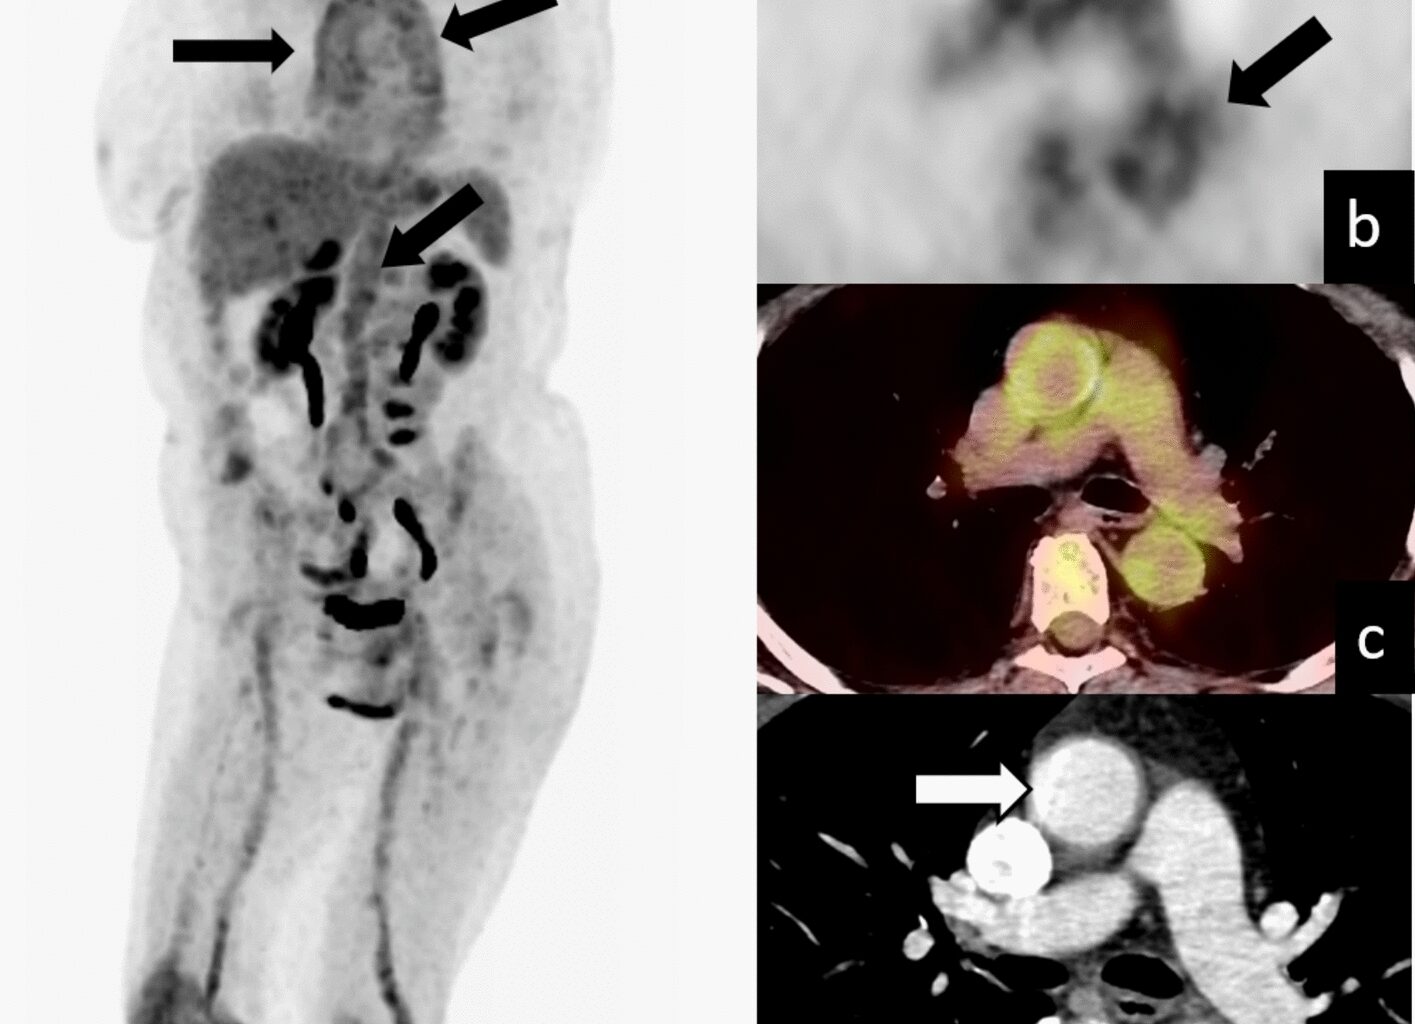

Murakami M, Morikage N, Samura M, Yamashita O, Suehiro K, Hamano K (2014) Fluorine-18-fluorodeoxyglucose positron emission tomography-computed tomography for diagnosis of infected aortic aneurysms. Ann Vasc Surg 28:575–578

Ahpin C, de Oliveira Brito JB, Chow B, Leung E (2023) Aortitis and coronary artery vasculitis of unusual etiology: IgG4-related disease defined by 18F-fluorodeoxyglucose positron emission tomography (FDG-PET). J Nucl Cardiol 30:413–416

Piva TM, de Faria Junior CR, Kato M, de Oliveira FR, Louzada P Jr, Wichert-Ana L (2023) Reversal of IgG4-related aortitis after treatment evidenced by [18F]FDG PET/CT. Clin Rheumatol 42:313–314

Chen N, Huang JB (2021) 18F-FDG PET/CT in the diagnosis of Takayasu arteritis: A case report. Radiol Case Rep 17:489–491

Walter MA, Melzer RA, Graf M, Tyndall A, Müller-Brand J, Nitzsche EU (2005) [18F]FDG-PET of giant-cell aortitis. Rheumatology (Oxford) 44:690–691